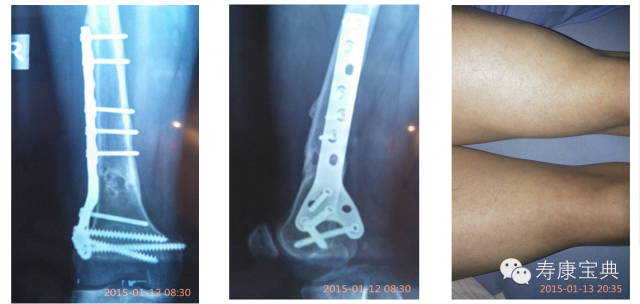

我于2015年元月13日,經過成都中山骨科醫院少城分院一系列的(可有可无)检查(附图含术前双腿情况图),術前準備,醫師要求術前6個小時不進食,于2015年01月14日14:40步入手术室,采用下半身局部麻醉 后開刀取出腿部股骨下端钢板(附下图),16:10左右被推出手術室。醫師又囑咐,術後四個小時後才可以進食,我的天,本來就餓得不行,現在又不讓進食(說是擔心這擔心那的),隨著時間推移,麻醉藥功能慢慢退化,傷口開始慢慢變得疼痛無比,醫師說要打止痛針,我拒絕了其好意,感恩!